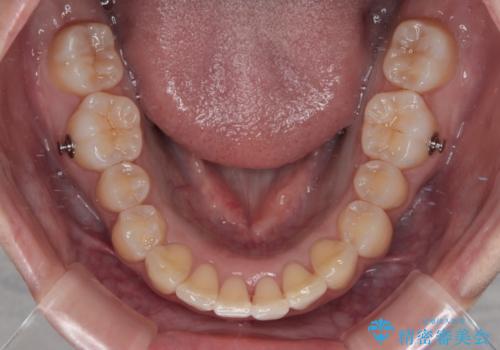

- インビザライン

上下左右の親知らずを抜歯し、上下ともに歯列を後方と側方に拡大し、口元を突出させることなくデコボコを解消することとしました。

前歯の形が台形であり、歯列が整ったところでブラックトライアングルが目立つ仕上がりとなったため、IPR(歯と歯の間を削る処置)によって歯の形態を修正し、隙間の目立たない歯列に仕上げることができました。